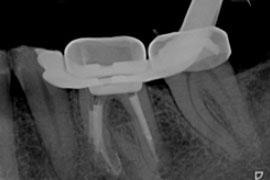

Entscheidend für den Erfolg der Wurzelkanalbehandlung ist die komplette Aufbereitung und Desinfektion des gesamten Wurzelkanalsystems. Die Aufbereitung der Kanäle bis an die Wurzelspitze erfolgt mit Stahl-Feilen, Ultraschall und hochflexiblen Nickel-Titan-Feilen. Dabei finden neben Handfeilen auch maschinelle Aufbereitungssysteme (drehmomentgesteuerte Feilen) ihre Anwendung. Die Bestimmung der Arbeitslänge erfolgt elektrometrisch und wird während der gesamten Therapie gemessen und kontrolliert.

Sehr lange, enge oder verzweigte Wurzelkanäle sind keine Seltenheit und die Desinfektion ist mit einem höheren Aufwand verbunden. Ein Dentalmikroskop, die elektrometrische Längenmessung, sowie ein Ultraschallgerät mit unterschiedlichen Arbeitsinstrumenten sind für den Erfolg der Behandlung wichtige Hilfsmittel.

elektrometrische Längenbestimmung an einem Eckzahn